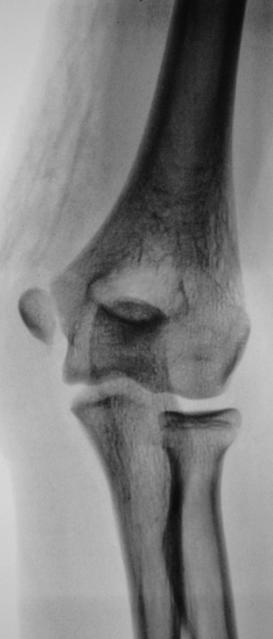

Пациент (подросток) направлен хирургом в рентгеновский какбинет для рентгенографии локтевого сустава. Накануне - травма. Произведено исследование. Ваше мнение коллеги по поводу наличия или отсутствия перелома.

Перелом мед.надмыщелка с небольшим смещением.

А апофизеолиза локтевоо отростка здесь нет? Зона роста неравномерная, резко сужена в верхнем отделе.

На здоровой руке обычная зона роста, на травмированной зона роста очень расширена. Это эпифизеолиз.